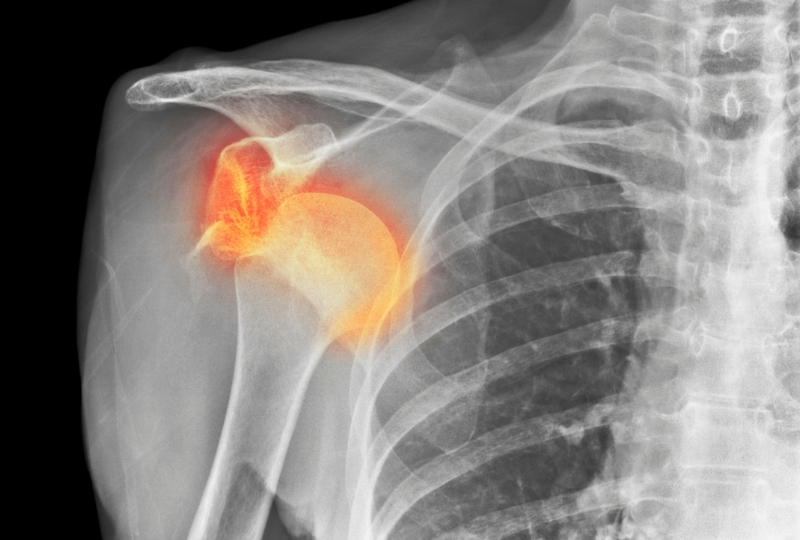

The rotator cuff assumes a unique role in the static and dynamic strength of the glenohumeral joint. The rotator cuff may tear because of the shoulder or dislocations disengagements.If the tear isn’t treated on time, it produces continuous pain, brokenness...

Shoulder instability is a condition that includes a loose shoulder joint that shifts around towards the socket after getting damaged due to an injury. It may result in sudden dislocation, slipping (subluxation), and may lead to severe joint pain & inflammation...

Total Shoulder Arthroplasty or Total shoulder replacement (TSR) is a procedure that is preferred a lot for curing shoulder arthritis. Though, after performing Primary Shoulder Arthroplasty, insufficiency of subscapularis...

What is a dislocated shoulder? It is an injury where the upper arm bone comes out of the cup-shaped...